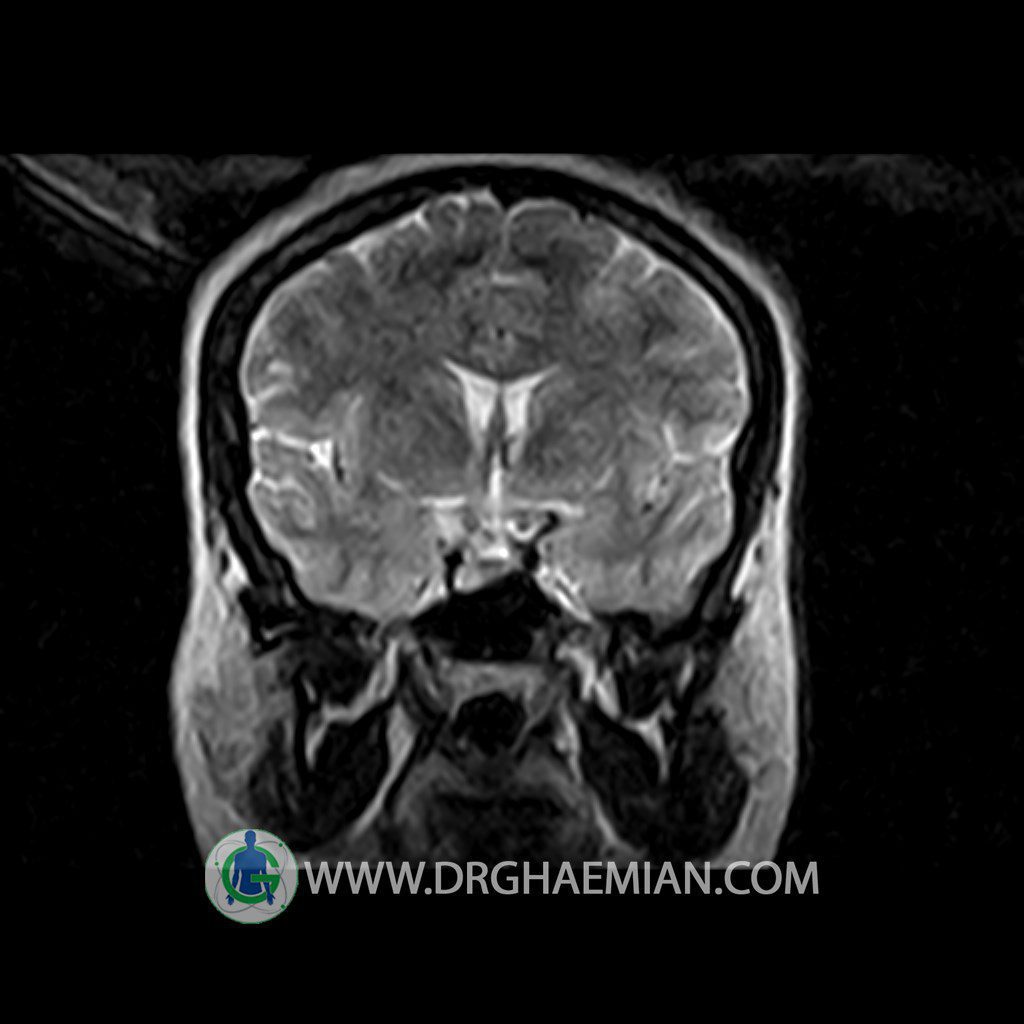

ام آر آی هیپوفیز یک روش تصویر برداری است که از غده هیپوفیز (غده ایی کوچک در مغز که هرومون ها و دیگر غدد بدن را کنترل می کند) و ناحیه های پیرامونش در مغز تصاویری ایجاد می کند. در این کیس سلای نسبتا خالی در ناحیه هیپوفیز بیمار مشاهده می شود.

– Extension of suprasella cistern to sella with thin pituitary gland in floor of sella ( partial empty sella )

is seen